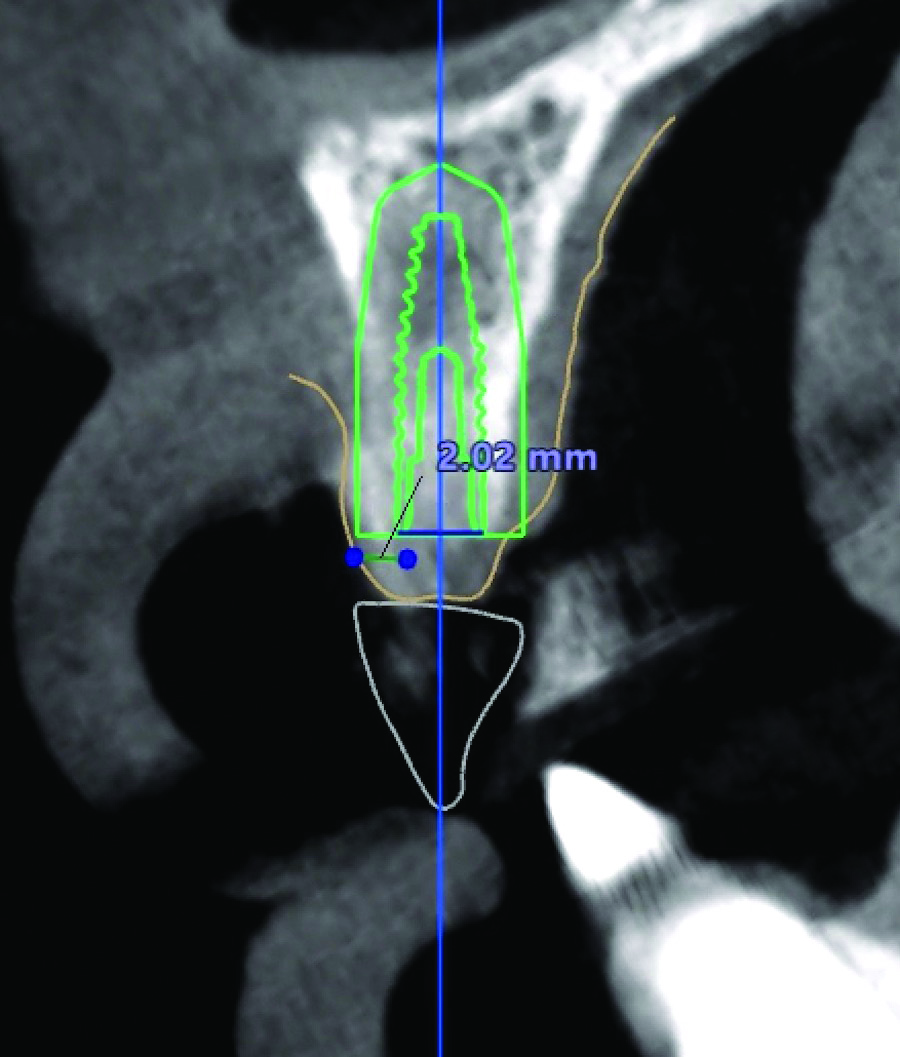

Fig 4. Digital tooth setup; the digital scan in Fig 2 was superimposed with a CBCT. The blue dots with green horizontal lines indicate MT measurements (2.04 mm and 2.02 mm). The simulated implant (green diagram of a dental implant with threads) and safety zone (green outline around the diagram of the implant) are overlaid on a cross-sectional image of the alveolar ridge. The red circle indicates the inferior alveolar nerve canal.

Figure 4

An example of an implant treatment planning case is presented in Figure 2 and Figure 4, with Figure 2 showing a digital scan of a mandibular arch that includes a missing tooth No. 19. The scan shows there was adequate KMW (>2 mm) at the No. 19 area. The digital scan of No. 19 was superimposed with a cone-beam computed tomography (CBCT) scan to analyze the future implant site. Upon superimposition, the MT could be measured at any surface (Figure 4). MT at the direct buccal and direct lingual aspects of the peri-implant mucosa was measured at >2 mm. The simulated future implant placement and the outlined safety zone of 1.5 mm radially and 2 mm apically around the implant indicate that the thickness of bone at the implant site was sufficient as planned. This case demonstrates there was enough KMW, bone thickness, and MT to proceed with implant placement.